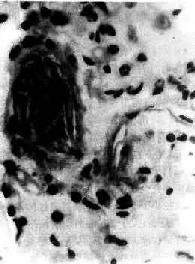

羊水栓塞(amniotic fluid embolism)是分娩过程中一种较罕见的疾患。在分娩过程中,如羊膜破裂,尤其又有胎儿头阻塞阴道口时,子宫收缩可将羊水压入破裂的子宫壁静脉窦内,羊水成分可由子宫静脉进入肺循环,在肺动脉分支及毛细血管内引起羊水栓塞。少量羊水可通过肺毛细血管进入大循环引起多数器官小血管的栓塞。镜下,羊水栓塞的证据是在小动脉和毛细血管内发现羊水成分:角化上皮,胎毛,胎脂,胎粪和粘液(图3-9)。本病发病急骤,产妇出现紫绀、呼吸困难和休克,绝大多数导致死亡。羊水成分栓塞肺血管所致的肺循环机械性阻塞,实不足以解释上述症状,因此过敏性休克、DIC、羊水液体内所含的血管活性物质进入血液引起血管反应可能是致死的原因。羊水具有凝血致活酶作用,可引起DIC,一些羊水栓塞病例,肺微血管内有纤维素性血栓存在。

肺羊水栓塞

图3-9 肺羊水栓塞

小血管内有角化上皮